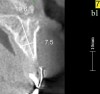

Figure 2  Identification of sufficient inter-radicular space: The radiographic representation of inter-radicular space (Fig 2) reveals abundant space for a single-tooth implant; at the alveolar crest, > 6 mm of interproximal space is available for placement of a 4-mm implant without encroaching on bone and periodontal ligament at the adjacent teeth. The 5-year-follow-up radiograph (Fig 3) reveals the interproximal maintenance of bone at this implant/abutment interface and adjacent teeth, in part due to proper planning and implant placement.

Figure 2

Figure 3  Identification of sufficient inter-radicular space: The radiographic representation of inter-radicular space (Fig 2) reveals abundant space for a single-tooth implant; at the alveolar crest, > 6 mm of interproximal space is available for placement of a 4-mm implant without encroaching on bone and periodontal ligament at the adjacent teeth. The 5-year-follow-up radiograph (Fig 3) reveals the interproximal maintenance of bone at this implant/abutment interface and adjacent teeth, in part due to proper planning and implant placement.

Figure 3